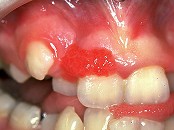

1.组图是牙龈瘤患者,有关此病的描述不正确的是 ( )![]() ![]() ![]() ![]() |